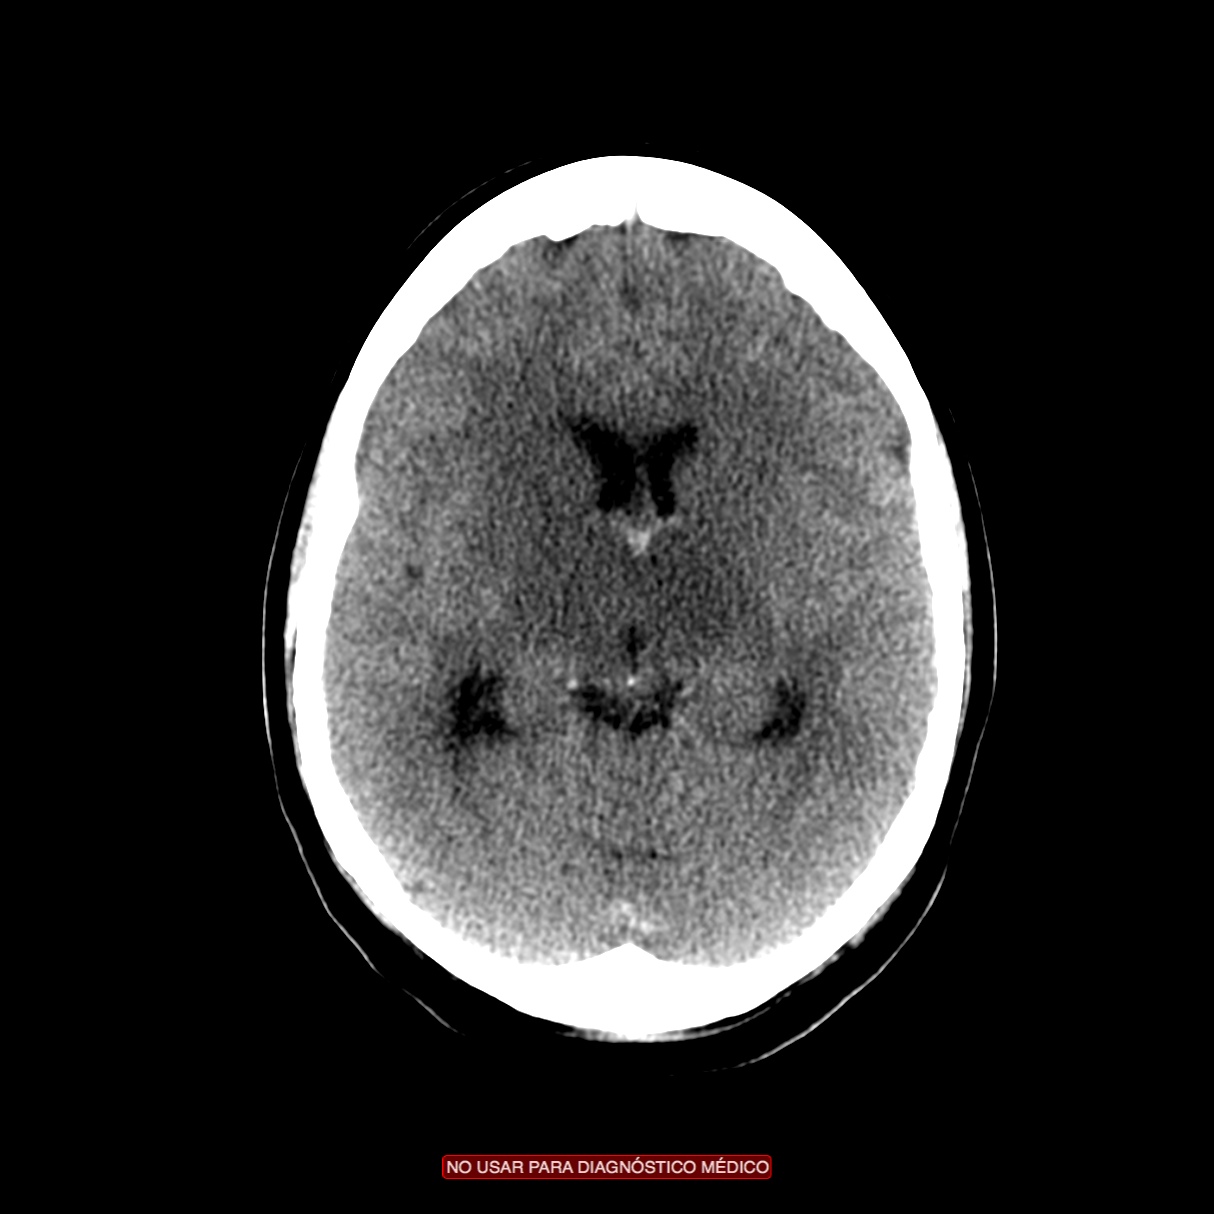

Se decide ingreso de la paciente para estudio y, ante el incremento de la cefalea y empeoramiento del estado general, se realiza nuevo TC de cráneo sin contraste. Veámos las imágenes.

1- TAC SIN CONTRASTE:

Se realiza para descartar otros procesos como infartos, tumores o infecciones.

- Signos directos: Cuerda Hiperdensa. En caso de trombo en las venas corticales, se observa el signo de la cuerda hiperdensa intraluminal. El trombo puede permancer hiperdenso 2 semanas para luego hacerse isodenso. La S y E de este signo son bajas.

- Signos indirectos: Cambios en el parénquima debido a la isquemia por perturbación del flujo venoso, produciéndose edema, infartos o hemorragias. Los infartos no hemorrágicos son las lesiones más frecuentes, suelen ser de localización subcortical, no sigue una distribución arterial y se localiza en las inmediaciones del seno afectado. Una afectación del SSS (el más frecuente) produce afectación bilateral en los territorios frontales, parietales y occipitales. Una afectación del ST afecta los lóbulos temporales. El seno recto afectado produce lesión profunda, en el tálamo. Los infartos hemorrágicos son menos frecuentes, se han descrito sangrados subdurales, subaracnoideos e incluso abiertos a ventrículos. El edema que se produce puede originar efecto masa con desplazamiento de la línea media e incluso disminución de ventrículos (dificil de valorar en jóvenes). La hidrocefalia marcada no se suele producir.